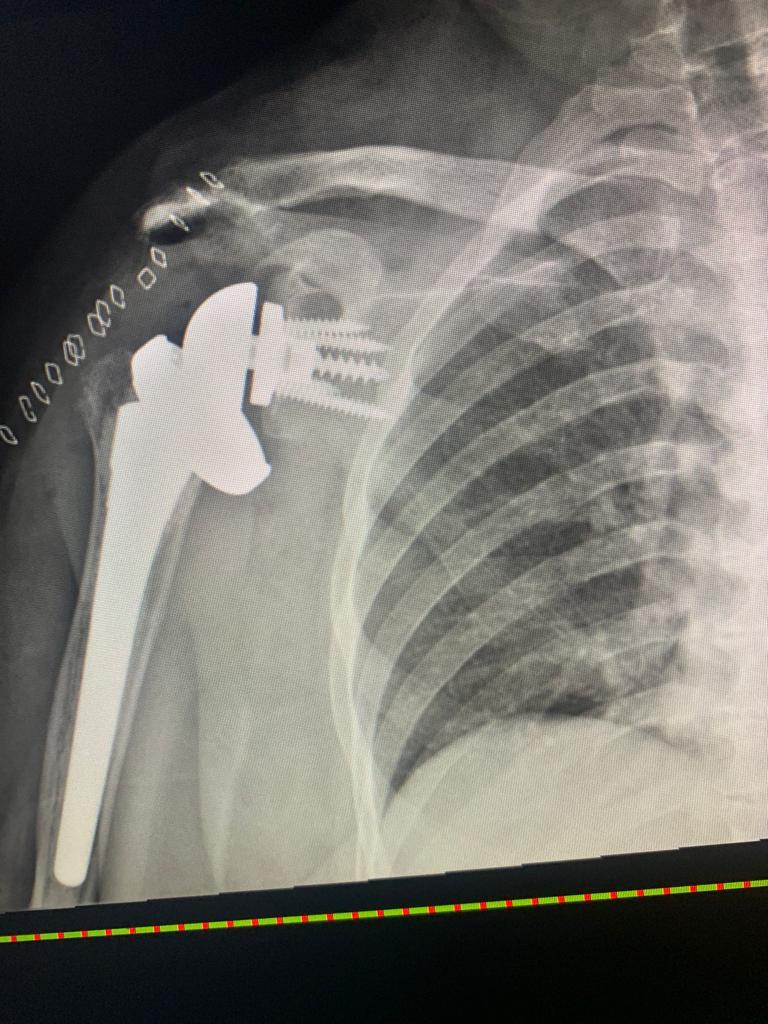

عملية نادرة - كتف صناعي معكوس- ينهي معاناتها من آلم مزمن بالكتف

قرر بعدها الفريق الطبي إجراء عملية عبارة عن تركيب مفصل كتف صناعي معكوس و تعتبر من العمليات النادرة في هذا المجال واستغرقت قرابة الساعتين  وبفضل من الله وتوفيقة تكللت العملية بنجاح وتمكنت المريضة من تحريك كتفها بشكل طبيعي وتخلصت من الآلام المبرحة التي كانت تلازمها وعودتها للممارسة حياتها طبيعية مع المتابعة مع قسم العلاج الطبيعي لاستكمال العلاج .